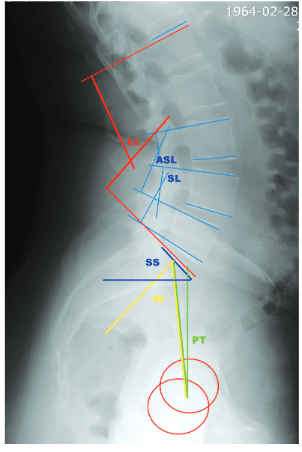

Оценка рентгенограмм проводилась независимым рентгенологом в системе Vidar Dicom Viewer 2.1. При этом оценивались следующие параметры: поясничный лордоз (LL) – угол между краниальными замыкательными пластинами L1 и S1 – позвонков (LLдо– до операции, LLп/о – после операции), угол падения таза (PI) – между линией, соединяющей центр вращения головок бедренных костей с центром замыкательной пластины S1, и перпендикуляром к плоскости верхней замыкательной пластины крестца; отклонение таза (PT)– угол между линией, соединяющей центр верхней замыкательной пластины S1 с центром вращения головок бедренных костей, и вертикальной линией (PTдо – до операции, PTп/о – после операции); наклон крестца (SS) – угол между верхней пластиной S1 и горизонтальной линией; сегментарный лордоз (SL) – угол между краниальной замыкательной пластиной верхнего и каудальной замыкательной пластиной нижнего позвонка на уровне спондилодеза; лордоз на смежном сегменте выше уровня вмешательства (ASL)– угол между краниальной пластиной позвонка, расположенного выше зоны спондилодеза, и каудальной пластиной верхнего позвонка зоны спондилодеза (рис. 1). Величина угловой коррекции рассчитывалась как разность между показателями LL, PT, SL или ASL до и после операции.